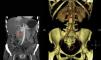

Presentamos el caso de una paciente de 41 años de edad diagnosticada de una cardiopatía congénita en la infancia consistente en: ventrículo único izquierdo de doble cámara con L-malposición de los grandes vasos e hipertensión pulmonar severa en situación Eisenmenger, con importante cianosis y eritrocitosis compensadora, en tratamiento con sildenafilo y bosentan. El diagnóstico se realizó a los 5 meses de edad y se desestimó la cirugía de reconstrucción cardiaca. Consultó por HTA, astenia, palpitaciones y malestar torácico, evidenciándose una descompensación de la insuficiencia cardiaca. Ante la sospecha de hipersecreción catecolamínica se realizó estudio hormonal que mostró metanefrina en orina de 24h: 215μg/24h (VN<341) y normetanefrina 2.491μg/24h (VN<444). El estudio de imagen realizado mediante TC abdominal mostró una masa retroperitoneal hipercaptante de 3×2cm en espacio interaorto-cava compatible con la existencia de un PG (fig. 1). El estudio gammagráfico de glándulas suprarrenales realizado con Iodo-123MIBG y fusión con imágenes de TC evidenció una zona de captación patológica del radiotrazador a nivel del espacio interaortocava coincidente con la lesión visualizada mediante TC y compatible con el diagnóstico de sospecha clínica, sin demostrarse otras lesiones a distancia. Se realizó estudio molecular mediante secuenciación de los exones codificantes y las regiones de unión exón-intrón de los genes: SDHD, SDHC, SDHB, VHL, SDHAF2, MAX y TMEM127, no encontrándose alteraciones. Tras el adecuado bloqueo alfa con doxazosina, y bajo estrecha vigilancia cardiológica fue sometida a tratamiento quirúrgico con resultado histológico de PG. No se identificó invasión capsular, ni linfovascular. La inmunohistoquímica reveló expresión intensa y difusa para cromogranina, sinaptofisina y tinción S100 en las zonas sustentaculares; índice de proliferación Ki-67: 1%. Tras la intervención se objetivó una concentración urinaria de normetanefrina dentro del rango de referencia, normalización de la TA, así como una mejoría clínica evidente.